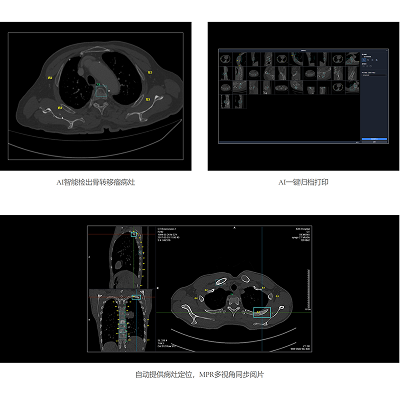

联影智能CT骨转移智能分析系统可秒级检出及分类原发骨肿瘤、溶骨性骨转移、成骨性骨转移、混合型骨转移与其他骨异常病灶,同时精准标识肋骨、椎体、盆骨位置,自动提供病灶定位信息,系统支持MPR三视图同步对比阅片、一键归档PACS功能,辅助医生高效、精准地完成肋骨、椎骨与盆骨骨疾病的诊断,避免漏诊。

联影智能CT骨转移智能分析系统支持多部位、多病灶类型的智能检出,自动标记骨头及定位病灶,极大降低了漏诊概率。其智能随访功能能自动精准配准图像,协助医生高效评估病情发展。系统还支持手动新增和编辑病灶,以及自动生成检查所见,有效提升了医生的工作效率和诊断准确性,为骨转移瘤的精准诊疗提供了强有力的支持。